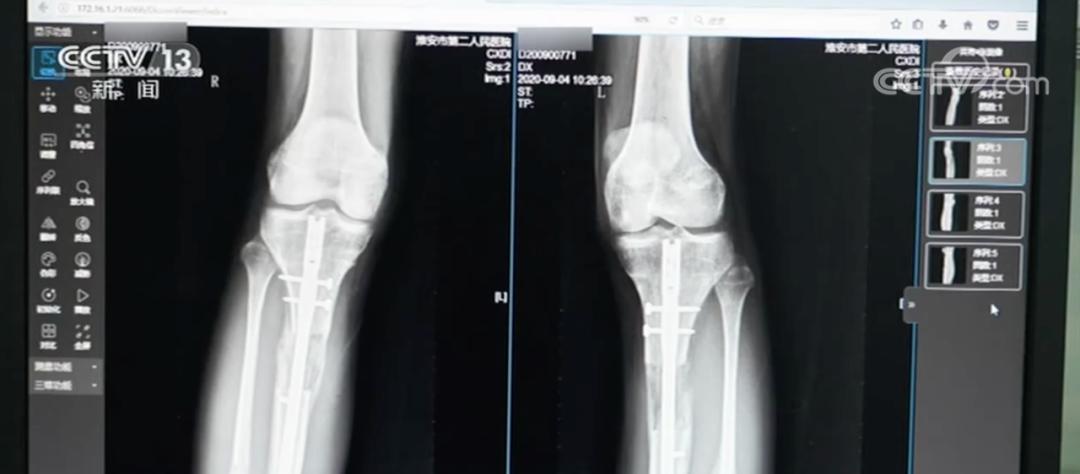

外架手术需要截断腿骨,用钢针穿透皮肤肌肉固定断骨,外部用圆环加固。术后每天需要调整支架旋钮拉伸双腿,全程需要一年半时间。内置手术则是沿腿骨植入电磁驱动髓内延长钉,通过体外遥控牵引,术后仅留2厘米微小疤痕且恢复期只有3个月时间。

如今,她体内的髓内钉至今仍未取出,因为取出手术可能引发二次骨折。更令她担忧的是,内置物中的磁铁成分可能会生锈,内固定装置还有断裂风险,小梦直言:“就像有颗定时炸弹藏在身体里”。

虽然小梦后续在国内接受了X型腿矫正手术,但效果并不理想。“我的腿脚经常酸疼,走路时间长了就会感到疲劳和僵硬,就像腿上绑着沙袋一样,断骨处也很疼,我不能像正常人一样起身、蹲下。”